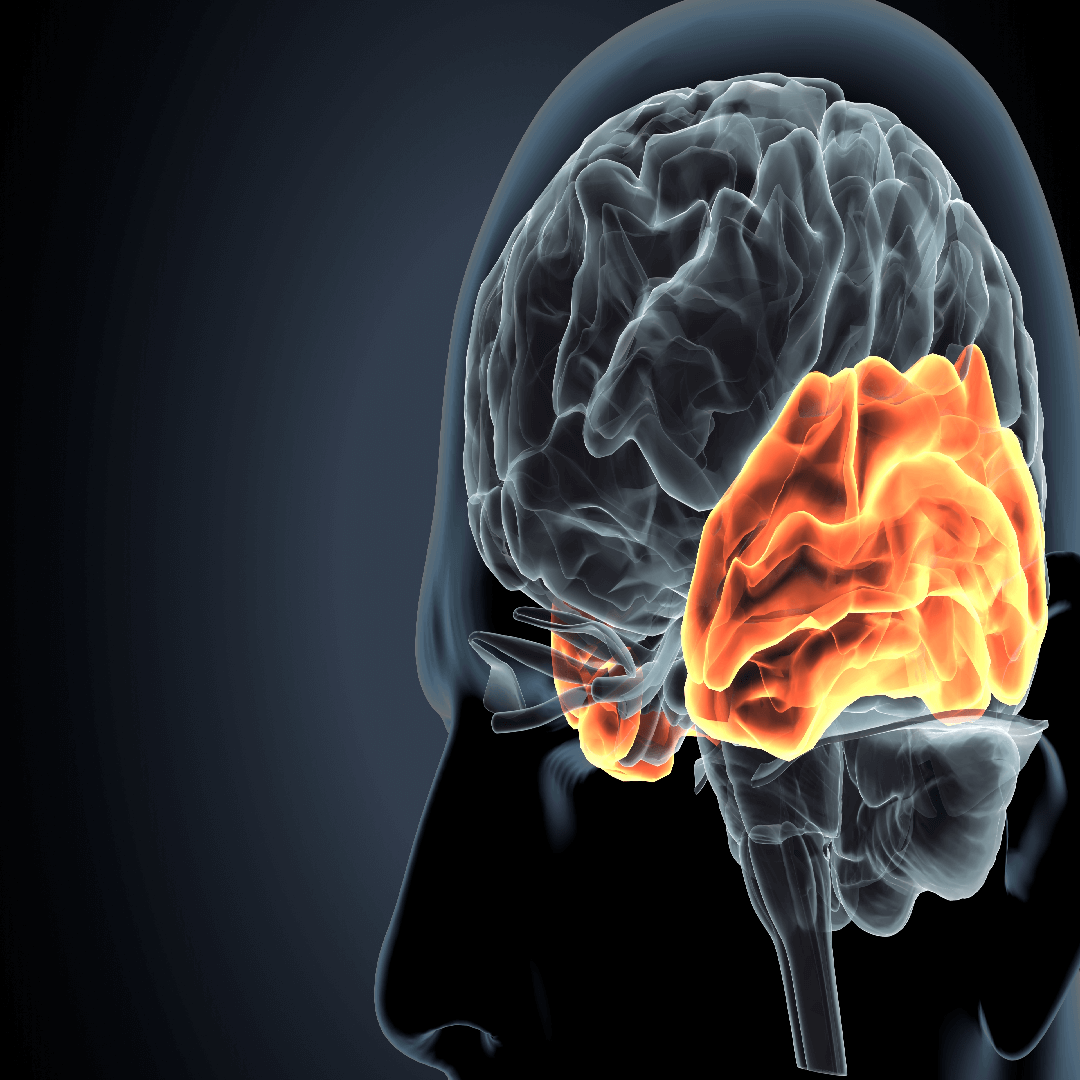

What Is a Brain Tumor and Why Is Specialist Care Important?

A brain tumor is a mass of abnormal cells growing within the brain or nearby structures. It can be either benign (non-cancerous) or malignant (cancerous). These tumors can affect brain function, depending on their size and location, and symptoms often include:

Because the brain controls vital body functions, any tumor — big or small — should be evaluated by a neurosurgical expert with access to advanced imaging and surgical tools.